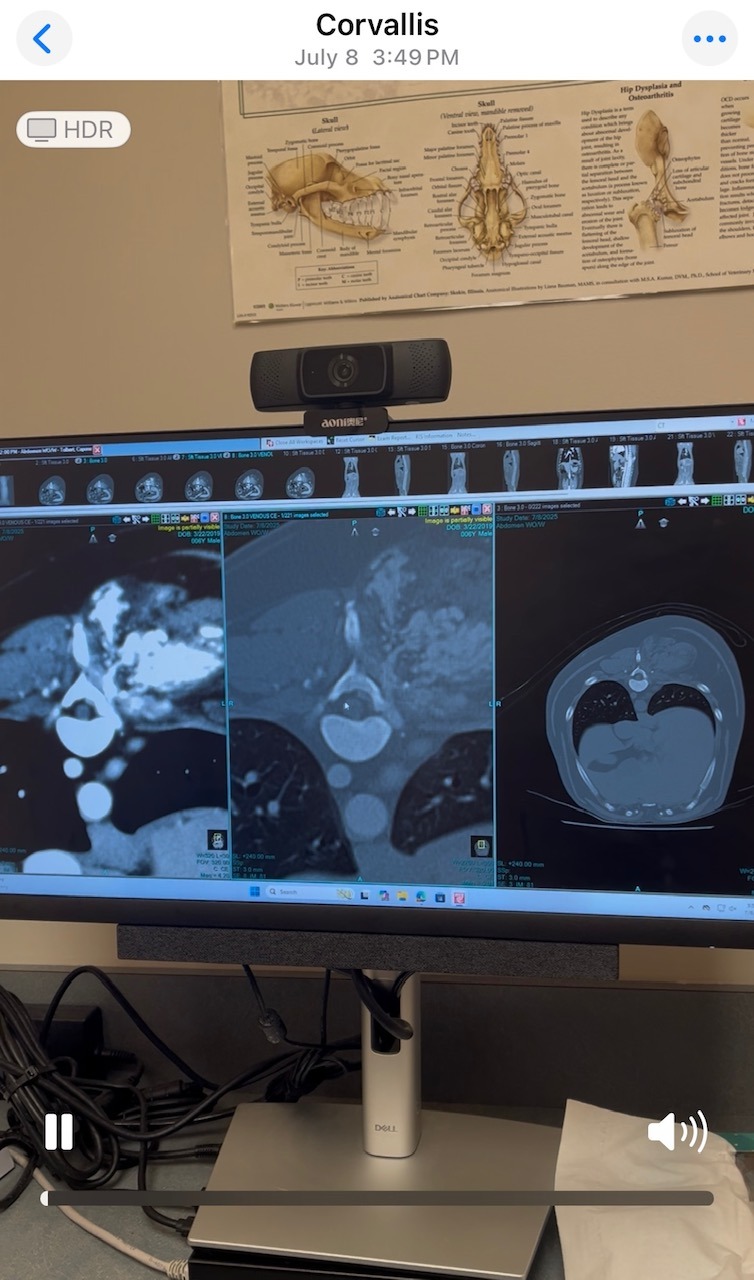

I am trying to raise money to pay for my dog's veterinary care. My dog, Capone, is a six-year-old Australian Shepherd/Blue Heeler mix who has a mass on his back.

To provide some context, I took him to his vet when we noticed the lump, and they did an X-ray but found nothing. I was then referred to OSU Animal Teaching Hospital for additional care and a CT scan. They found the lump was full of blood with hundreds of blood vessels feeding into it. They were unsure if it was a tumor or some sort of malformation. They told us to come back in 3 months for another CT so they could see if it was growing. During this time, we were monitoring Capone at home, and he was starting to have mobility issues with his back legs. After the new CT at OSU, they found the mass had grown and was pushing his spinal column and cord. Our options at OSU have run out. The mass is not presenting as cancer, so they are leaning more towards an arteriovenous malformation. They referred us to UC Davis, where they specialize in these malformations. Our two options are to let Capone continue living his life, provide interventions to the best of our ability and eventually euthanize him, or go see this vet in California, where they believe they can surgically intervene and relieve the pressure off his back and hopefully bring back his mobility. Capone is our son and my soul dog. There is nothing in this world that I would not give to fix this and help him regain his health. We have been quoted anywhere from $12-17K, and we are short on our savings. With your help, we can provide Capone the opportunity to live a longer life and rehabilitate him back to good health. Our appointment at UC Davis is September 22, 2025. If you cannot donate, please share this with others and keep my baby in your prayers.